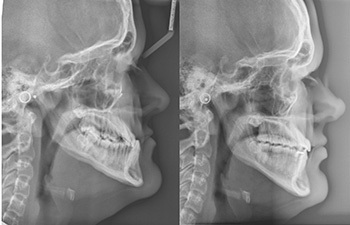

In CO, which I will refer to as position (a), Ethan showed a complete anterior crossbite with Class 3 occlusion. When Ethan rotated his mandible down and back (including the slide out of CO), his incisors could come to an edge-to-edge position when he opened to a 3 mm anterior open-bite position. I will refer to this as position (b). See Figs. 2a and 2b to compare these positions facially.

In Class 3 patients like Ethan (those who have a CO/CR slide and can facially tolerate or benefit from a vertical increase), in addition to the facial change, the occlusal difference from (a) to (b) is quite significant. The mandible sliding down and back decreases the magnitude of both the A-P and the transverse malocclusions.

In regard to A-P, as the mandible rotates or slides down and back, the mandibular occlusion moves posteriorly (toward Class 1) into a less severe Class 3 position. Thus the A-P burden has been decreased.

In regard to the transverse, again as the mandible rotates or slides down and back, the mandibular arch moves posteriorly into a wider part of the maxillary arch. In this position, the transverse burden to overcome has also been decreased. In short, after the CO/CR slide and in the new vertical position, the macro (facial) aesthetics of the case are greatly improved, and the severity of the malocclusion, while still present, is significantly diminished.

Figure 6 shows progress through month 16. Upper incisors were not flipped, and SAP bracket positioning (à la Tom Pitts) was used to cheat the occlusal plane in favor of more upper incisor show (Class 3 patients are quite often deficient in vertical incisor show). A noticeable change in the occlusal plane is apparent on cephalometric comparison, reflective of this SAP bracket positioning. This increased vertical incisor show is expressed well within his now decompensated (taller) smile window allowed by (b).